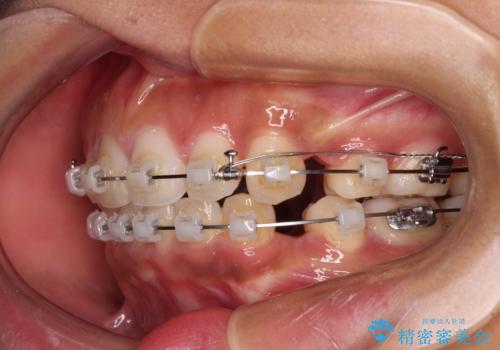

- クリアブラケット

- 2年6ヶ月

- 10-30回

口元の突出感を改善するため、上下左右第一小臼歯4本の抜歯を行い、ワイヤー装置による矯正治療を行うこととしました。